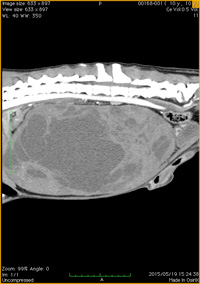

巨大な肝臓腫瘤